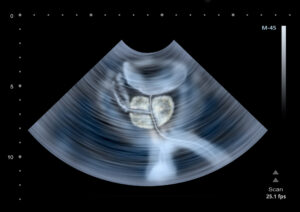

The prostate